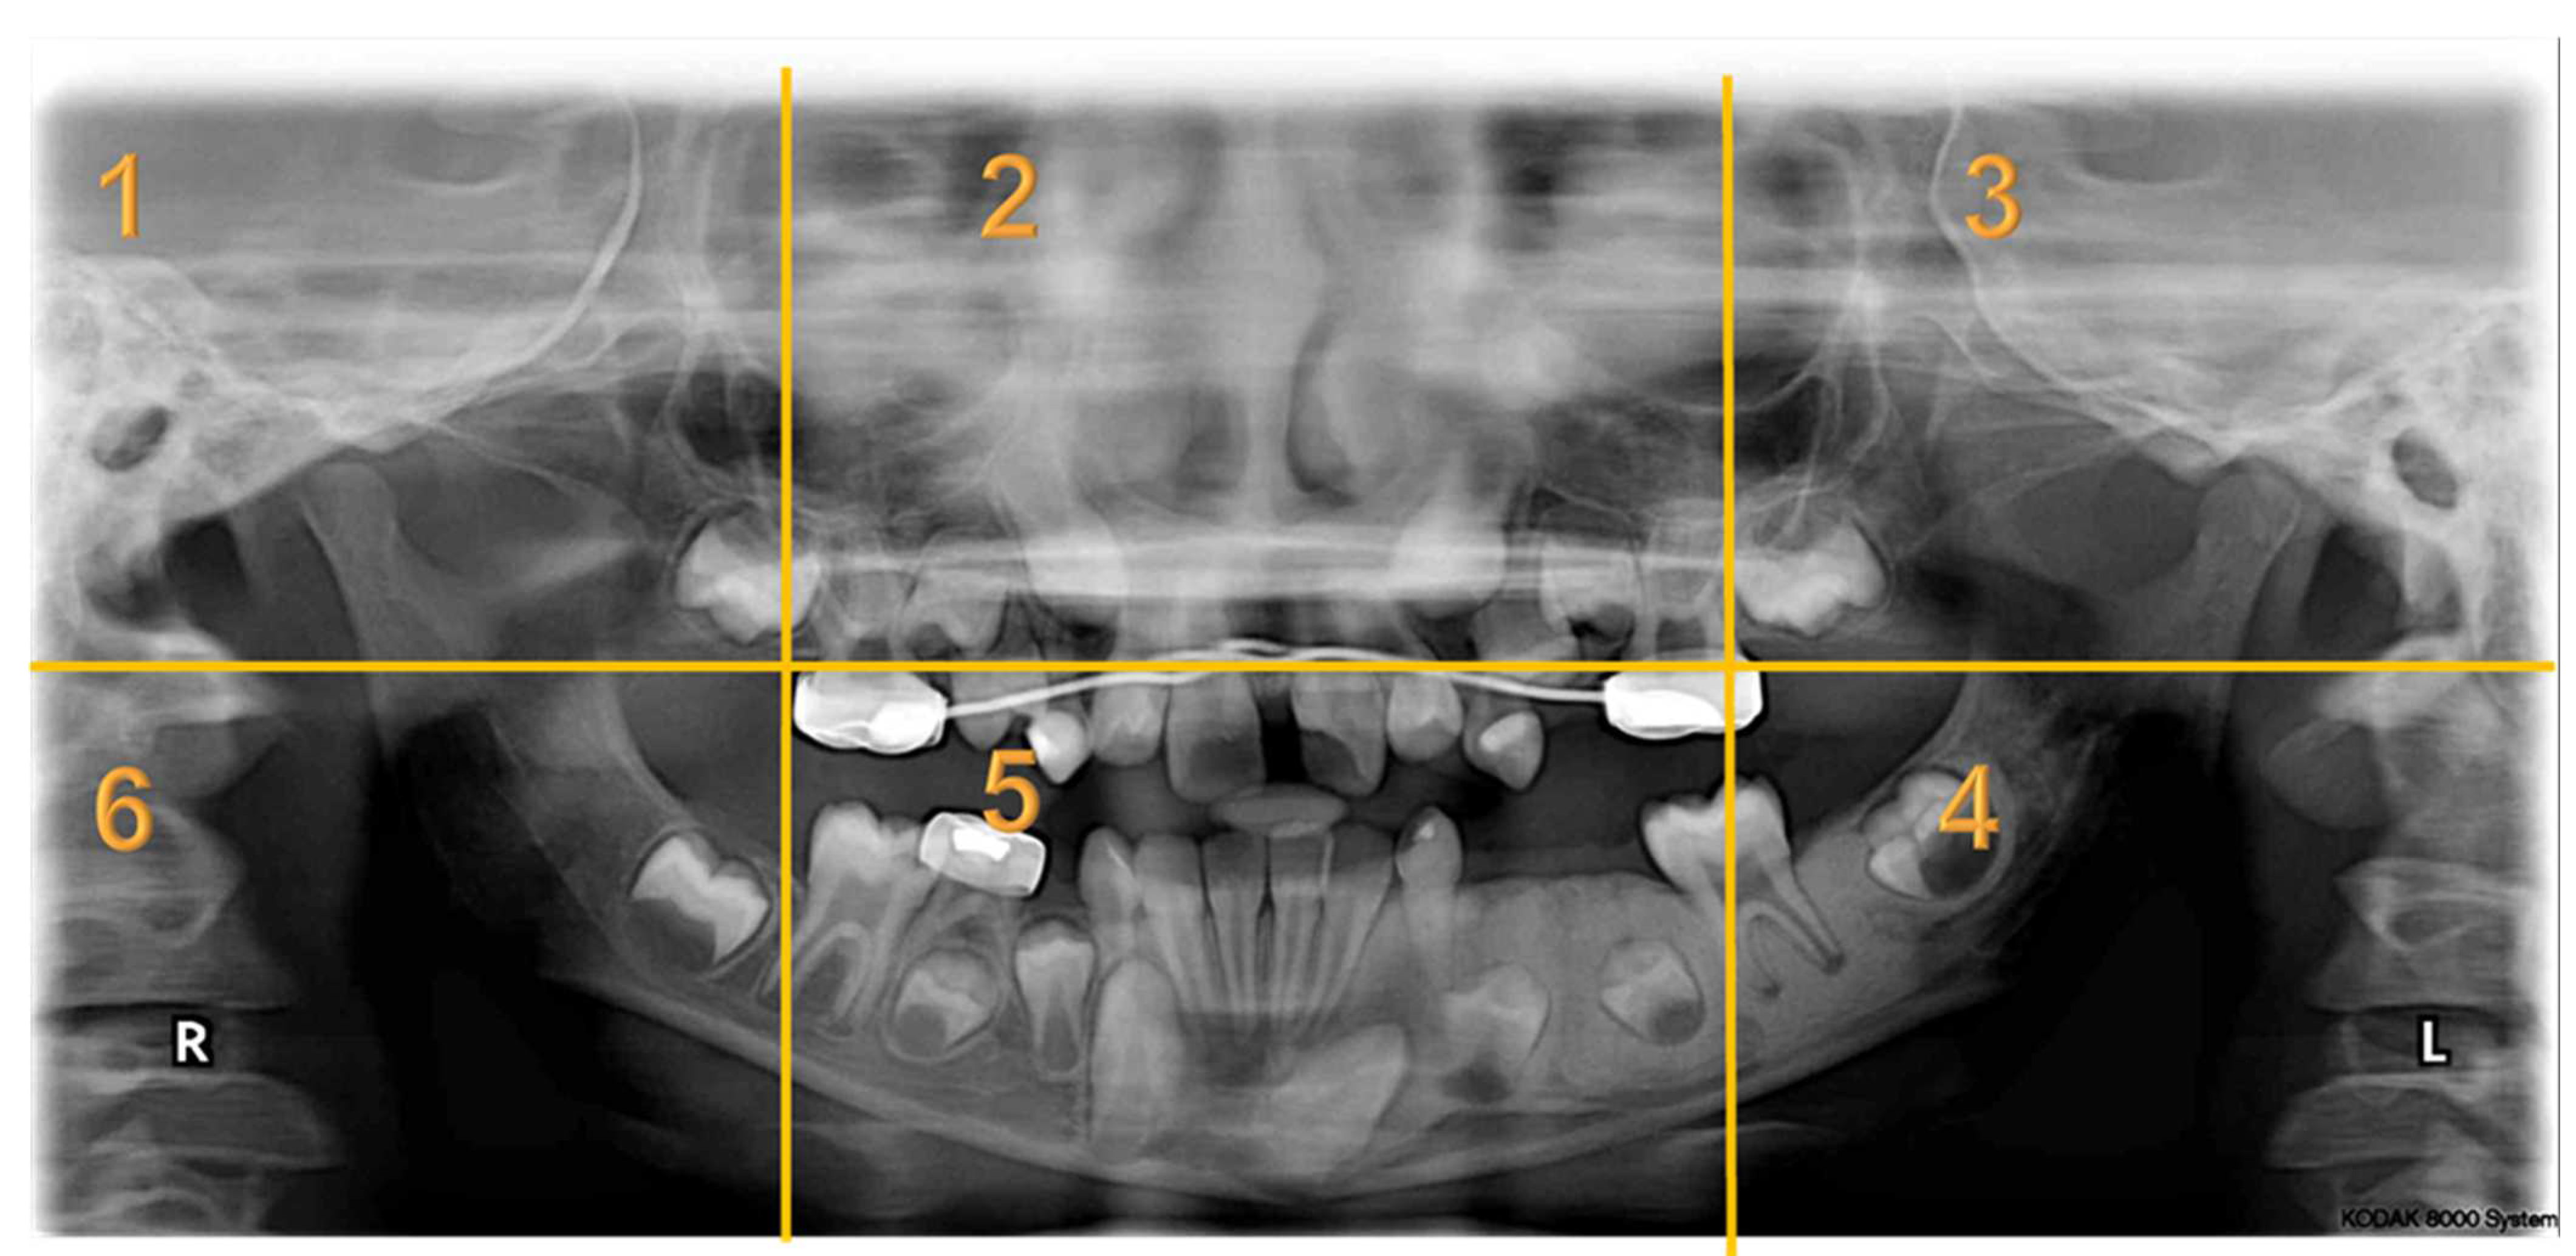

Appendix A. Radiographs Included in the Study

- Each panoramic radiograph displayed will be divided into sextants by yellow lines.

| Radiographs with Abnormalities | Number of Sextants Involved | Number of AOI a | Number of Participants | Total Recorded Observation b |

|---|---|---|---|---|

| Radiograph 1 | Multiple | 3 | 30 | 90 |

| Radiograph 2 | Multiple | 8 | 30 | 240 |

| Radiograph 3 | Single | 2 | 30 | 60 |

| Radiograph 4 | Single | 2 | 30 | 60 |

| Radiograph 5 | Single | 1 | 30 | 30 |

| Radiograph 6 | Single | 1 | 30 | 30 |

| Radiograph 7 | Single | 1 | 30 | 30 |

| Overall Observations | 540 |